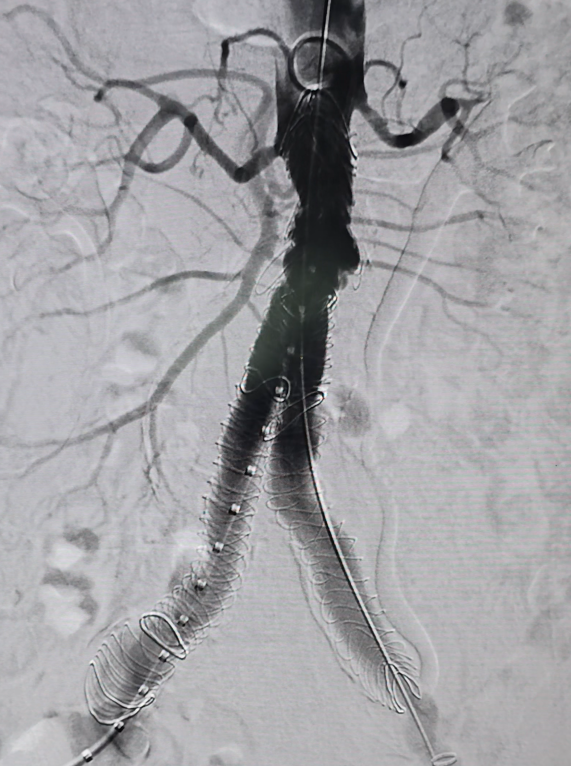

Exclusion de Aneurismas

Los aneurismas son dilataciones anormales de las arterias que debilitan una sección específica, lo que aumenta el riesgo de ruptura.

Existen dos métodos principales para la reparación de aneurismas: la reparación abierta y la reparación endovascular (EVAR).

En la reparación abierta, se accede a la cavidad abdominal para exponer completamente la arteria afectada. Luego, se coloca un injerto sintético en el sitio del aneurisma para restaurar la integridad arterial.

La reparación endovascular (EVAR) sigue el mismo principio de exclusión del aneurisma, pero se realiza a través de pequeñas punciones en las arterias. A través de estas punciones, se introducen catéteres para colocar una prótesis y reforzar la arteria desde el interior.